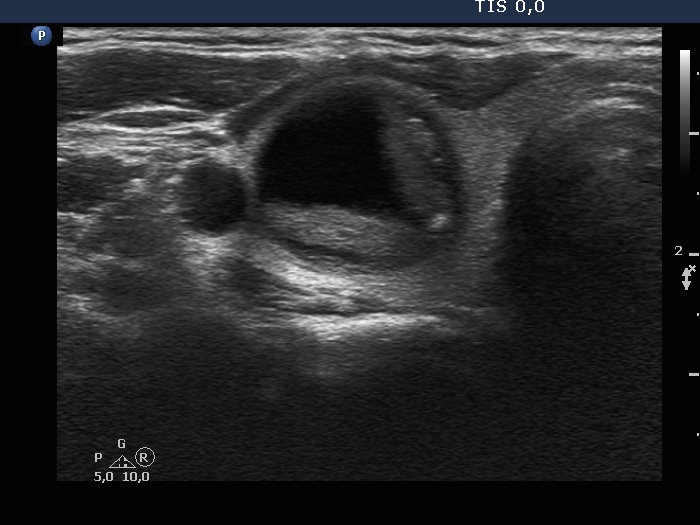

The composition of the nodulen - case 399 (ultrasonographic picture 2)

Right lobe, another transverse scan.